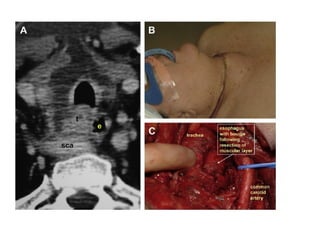

   Si sospechamos de un tumor localmente invasivo

debemos de agregar a los estudios preoperatorios

habituales una TAC contrastada o RM (extensión del

tumor, metástasis y afección ganglionar), valorar el

uso de endoscopía para visualizar tráquea y esófago.

   Dralle y col. Clasifica 6 tipos de resección laringo-

traqueal, dependiendo de la extensión y la localización

de la invasión visceral.

 Resección tipo rasurado (no reseca todas las capas de pared)

 Resección en ventana (incluye todas las capas de la pared, con

diversas técnicas de cierre). Se describe que se puede resecar

hasta 1/3 de la circunferencia traqueal sin comprometer la vía

aérea.

 Resección en manga (resección circunferencial total, con o sin

liberación laríngea.)

Complejo laringo-traqueal  Síntomas en 28% afección laríngea y 18% traqueal.  Se presenta disnea cuando la luz de la tráquea se reduce más del 50%.  La enfermedad puede invadir la vía aérea ya sea directamente por el tumor o por invasión extra- ganglionar.

 En lainvasión traqueal el tumor puede ser subestimado ya que tiende a ser mas circunferencial más que longitudinal.  Dependiendo del estadio de invasión al complejo laringo-traqueal, se pueden realizar diversos procedimientos para la resección del tumor macroscópico y tratar de ser en lo posible conservadores.  Resección tipo rasurado (no reseca todas las capas de pared)  Resección en ventana (incluye todas las capas de la pared, con diversas técnicas de cierre). Se describe que se puede resecar hasta 1/3 de la circunferencia traqueal sin comprometer la vía aérea.  Resección en manga (resección circunferencial total, con o sin liberación laríngea.)